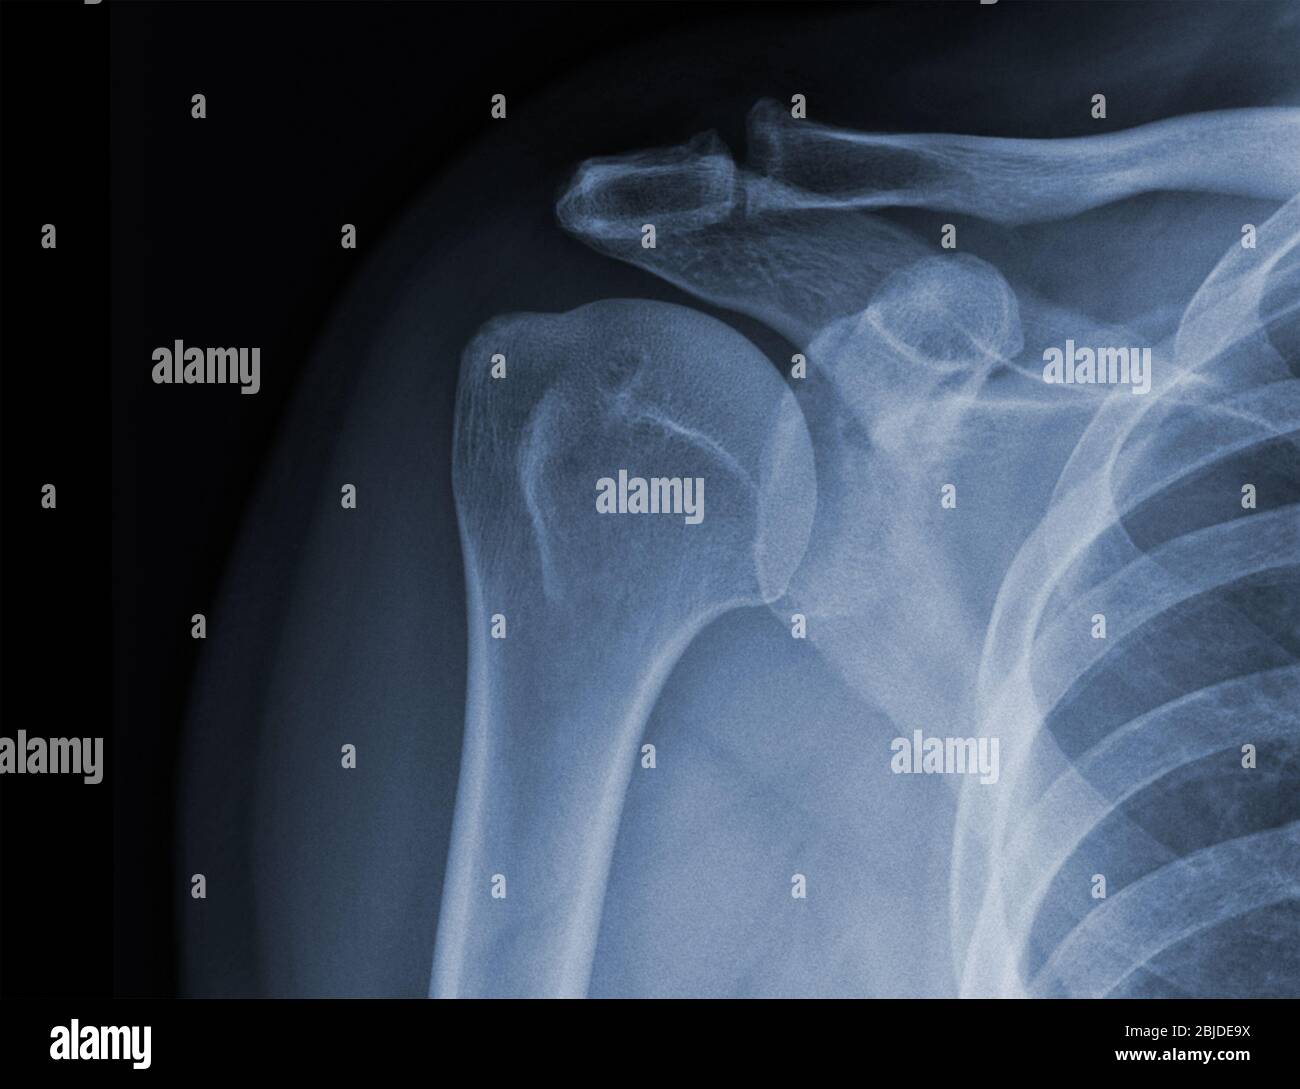

Xray shoulder radiograph show state of injury Stock Photo Alamy Shoulder Trauma X Ray Views The american college of radiology recommends at least 3 views for acute traumatic shoulder pain [5]: Provides better detail of cortical and trabecular bone structures than mri at cost of higher radiation exposure. This projection can be used as a. The shoulder series is fundamentally composed of two orthogonal views of the glenohumeral joint including the entire. The 'shoulder' joint. Shoulder Trauma X Ray Views.